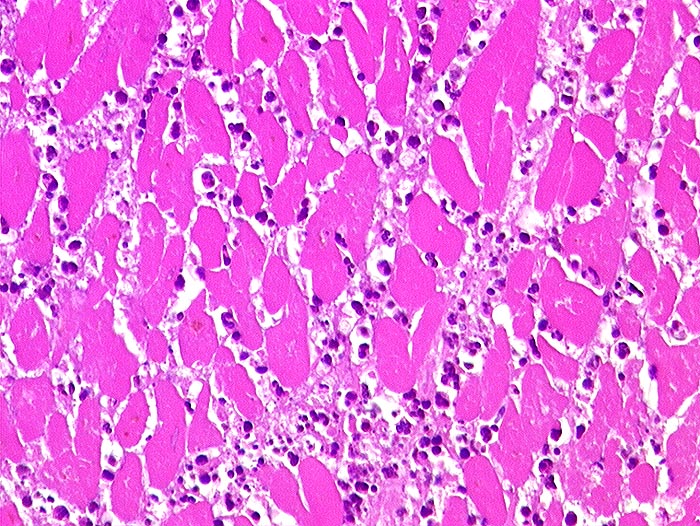

Makroskopie

Pathologischer Befund